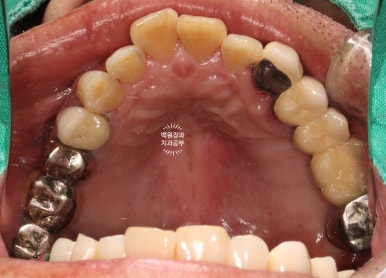

처음 내원하셨을 때 치과용 파노라마 소견입니다.

아래는 이가 하나도 없어 얼마 전 다른 치과에서 제작한 전체틀니를 사용하고 계셨고,

위 어금니는 브릿지로 되어있는데 만성치주염으로 흔들거리는 상황이었습니다.

저희 치과에 내원하셨을 당시 입안 사진입니다.

사실 사진만으로는 그 불편함을 느끼기가 어려우실텐데요, 아래는 비교적 최근에 제작된 깔끔한 전체틀니를 사용하고 계셨고, 위 어금니는 만성치주염에 이환되긴 했지만 형태를 모두 갖추고 있었습니다.